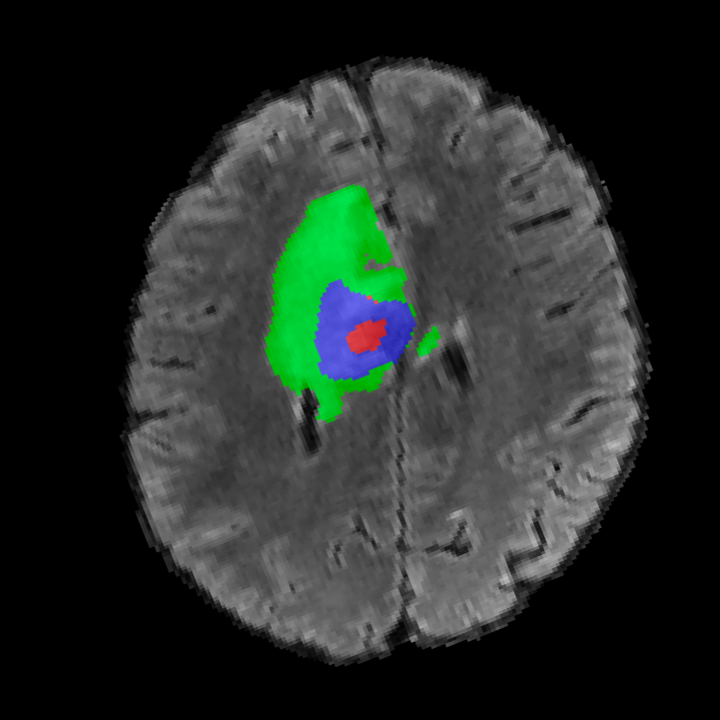

Tumour Information Preservation. For the brain tumor segmentation, we use a Swin UNETR model[28, 70], trained with random rotation, and intensity as data augmentation. On the test set with human ground-truth annotations (), the brain volumes generated from single slice input preserve the volume of the different tumour components (paired t-test, for all 3 classes). In Figure 4, we highlight the tumor profiles of the generated MRIs compared to the ground truth tumour profile. The real MRI Dice score in the test set is 85.15 while the generated MRIs from a single slice have a dice score of 83.09. This shows how the generated MRIs indeed preserve the tumor information and can act as an affordable and informative pseudo-MRI, before conducting an actual costly MRI examination in hospitals. More detailed results are provided in supplementary material.

On the test set with human ground-truth annotations (), the brain volumes generated from single slice input preserve the volume of the different tumour components (paired t-test, for all 3 classes) (see Table I). The real MRI Dice scores are put for reference to our generated MRIs. X-Diffusion outperforms baselines TPDM [39] and ScoreMRI [19] in tumour preservation (see Table I and Figure III). We ran experiments comparing the tumour segmentation Dice Score varying X-Diffusion configurations. The multi-slice input X-Diffusion achieves marginally better Dice Score than the single slice input model (83.47 83.09). We also ran experiments with slice input used for volume reconstruction intersecting or not with tumour. We observe on average a drop of 6% Dice Score (see Table I). Further away from the tumour the input slice for volume reconstruction is selected, we observe a linear decrease in tumour segmentation Dice Score with lowest value of 77.21 Dice Score (see Figure VI).